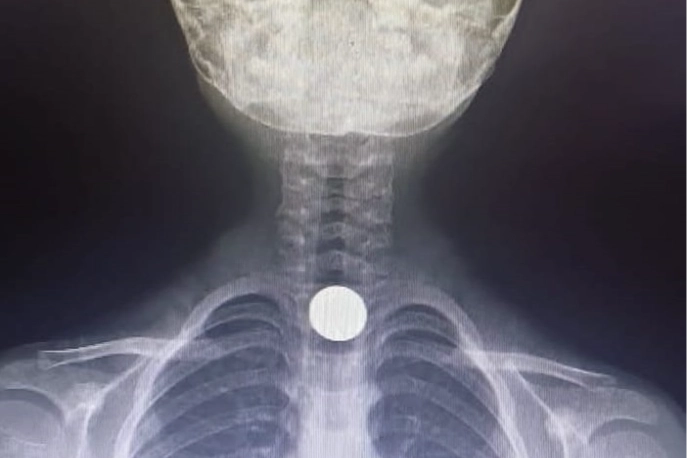

Tetkiklerde, yemek borusuna 50 kuruşluk madeni para kaçtığı tespit edilen Yusuf Z., ambulansla Bursa Yüksek İhtisas Eğitim ve Araştırma Hastanesi'ne sevk edildi.

Yusuf Z.'nin yemek borusundaki para, burada yapılan başarılı ameliyatla çıkartıldı.